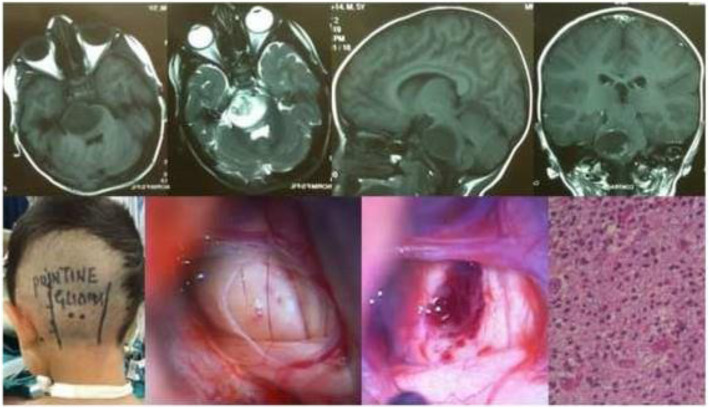

Fig. 5.

Pontine-glioma grade III in a 5-year-old male child. MR images and intra-operative micro-photographs and clinical photo in sitting position display left retro-mastoid approach and tumor decompression. Histological micrograph (H&E Stain; × 400) is seen